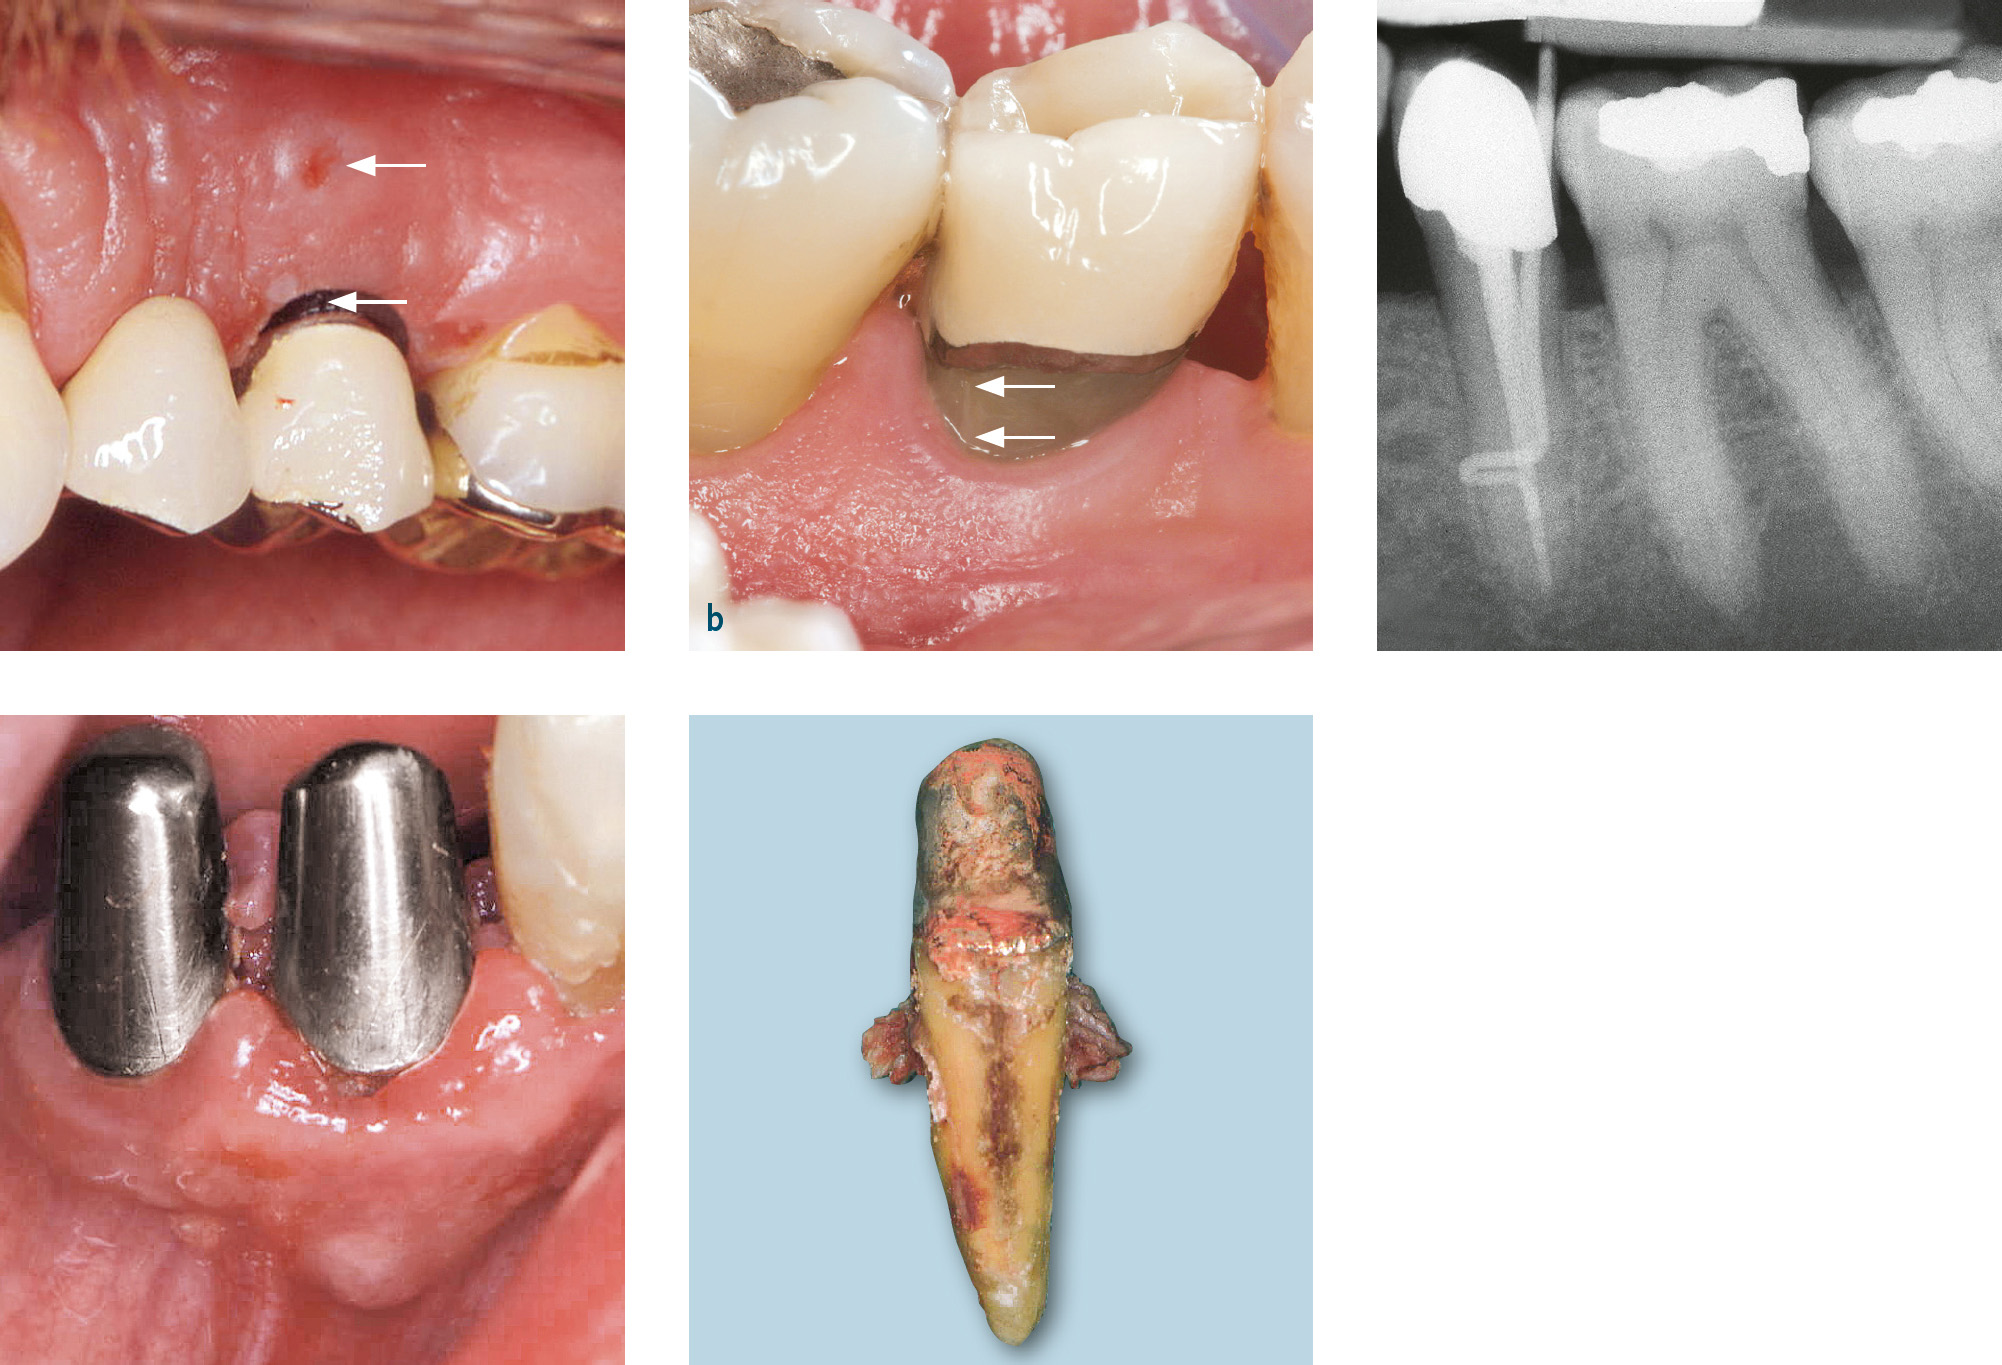

Die Differenzialdiagnose zwischen primär endodontaler Läsion bei partieller Pulpanekrose und tiefer primär parodontaler Läsion, die zu einem Parodontalabszess geführt hat, ist diffizil. Hilfreich ist es, bei der Röntgendiagnostik einen röntgenopaken Stift (z. B. Guttaperchapoint) in die Fistel/parodontale Tasche einzuführen (Abb. 7c, 8). So lässt sich häufig der Ursprung der Eiterung (z. B. periapikale Region) darstellen. Hinweise für eine primär endodontal verursachte Läsion sind kariöse Läsionen (Abb. 8b) oder pulpanahe Restaurationen und Kronen2. Bei etwa 10 % der Kronen kommt es in den ersten 10 Jahren nach Präparation zu Pulpanekrosen. Bei einem Patienten, der generell keine oder wenig Attachmentverluste oder Knochenabbau und nur isoliert an einer Stelle eine stark erhöhte Sondierungstiefe mit Suppuration aufweist (endodontal-parodontale Läsion ohne Beschädigung der Wurzel bei Patienten ohne Parodontitis: Grad 1), sprechen die Befunde für eine primär endodontale Läsion (Abb. 7c, 8). Ein Patient, der auch an anderen Stellen lokalisiert oder generalisiert tiefe Taschen sowie Knochenabbau zeigt, bei dem aber der Beschwerden bereitende Zahn endodontisch nicht vorgeschädigt ist, hat mit hoher Wahrscheinlichkeit eher ein primär parodontales Problem. Eine periapikale hypodense (radiotransluzente) Zone auf zweidimensionalen Röntgenbildern muss kein eindeutiger Hinweis auf eine Läsion primär endodontaler Genese sein. Die dreidimensionale Ausdehnung primär parodontaler Knochentaschen kann je nach Projektion periapikale Osteolysen vortäuschen (Abb. 9).

Abb. 8a, b Jugendlicher Patient mit Beschwerden an Zahn 26. Klinisch findet sich mesiobukkal 26 eine Sondierungstiefe von 11 mm mit Suppuration; der Zahn reagiert positiv auf Sensibilitätstest. Ein Vorbehandler hatte bereits die Diagnose Parodontalabszess gestellt und ein subgingivales Scaling durchgeführt, bevor er zur systematischen Parodontalbehandlung überwies. a) Panoramaschichtaufnahme: kein Anhalt auf Knochenabbau; b) Zahnfilm 26 mit Guttaperchapoint in der mesiobukkalen Tasche: mesial bis ins Dentin reichende Karies, der Guttaperchapoint reicht bis in die periapikale Region. Diagnose: akute Parodontitis periapicalis ausgehend von partieller Pulpanekrose an 26. Die Chance für ein Reattachment nach Wurzelkanalbehandlung war allerdings durch das subgingivale Scaling vergeben worden.